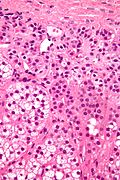

Spironolactone bodies are seen in the cortex of the adrenal gland in the context of long-term spironolcatone use.

• Location: zona glomerulosa (where aldosterone is produced).

• Appearance: eosinophilic spherical laminated whorls.